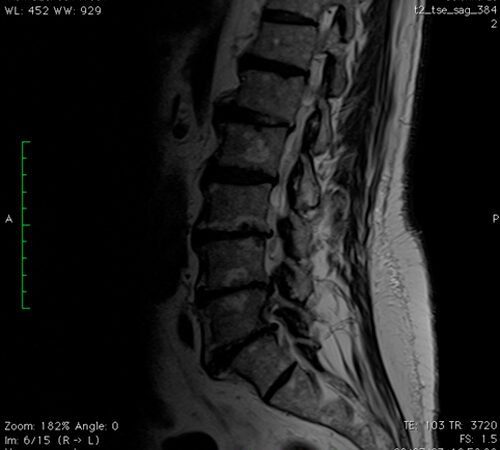

DIAGNOSI:

SPONDILOLISTESI LOMBARE DI II GRADO L5-S1

Risonanza magnetica pre-operatoria